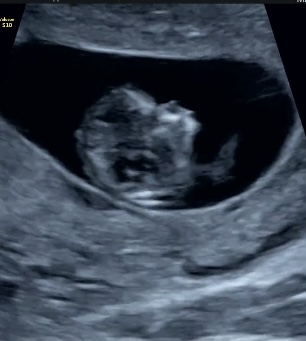

Тут 99% девочка Поздравляю

Алина, чётко виден бугорок ) Это девочка Сердцебиение у моих всегда одинаковые

РоМаШка, я сомневаюсь((( на скрининге на снимке ничего не видно, бугорка нет, ребёнок перекатился к датчику, не на спинке( и он такой по размеру, как мои сыновья, сердце 178удМ. У вас сыновья и дочь по параметрам отличалась(говорят девочки длиннее и головка у них меньше). Я смотрела параметры дочери, там совсем по другому, но она была больна, по этому наверно не информативно

Девочка